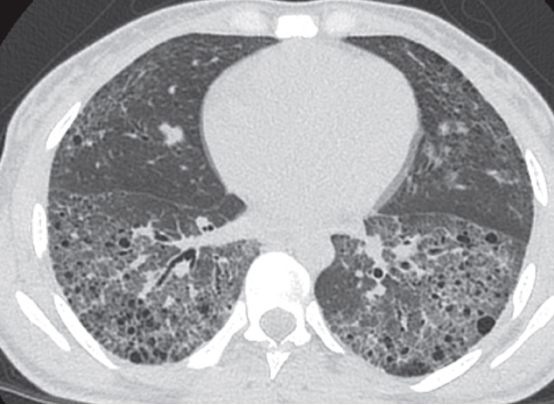

淋巴管平滑肌瘤病(LAM)是一种低度恶性肿瘤,最常发生育龄期妇女;LAM的特征是气道、血管和淋巴管周围不典型平滑肌细胞(LAM细胞)的增殖;LAM可以是一种独立的疾病,或与结节性硬化综合征有关,是由结节性硬化症1或2个基因突变引起的(7.8)。LAM最常见的呼吸表现包括运动时进行性呼吸困难和复发性气胸(高达70%的病例),以及较少见的咳嗽、咯血和乳糜胸(8)。LAM的囊肿通常是规则、薄壁的;通常直径为2-10毫米,广泛分布,数量不等,并被正常肺实质包围(图2A和2B)。(9)LAM囊肿的形成推测是由于LAM细胞在远端空腔扩张时阻塞终末细支气管,以及/或由于蛋白酶和蛋白酶抑制剂之间的不平衡导致肺实质降解。CT上还可发现间接征象,如气胸、肾血管平滑肌脂肪瘤、乳糜胸、乳糜腹水、腹部和盆腔淋巴血管平滑肌瘤(图2 C和D)。此外,还可出现规则的小叶中央结节,通常由多灶小结节性肺细胞增生引起,和不常见的磨玻璃影,继发于肺泡出血或淋巴管阻塞(3,9)。

2 一位女性LAM患者的胸部CT A轴位和B位冠状 位:弥漫性壁规则肺囊肿。C一名女性淋巴管平滑肌瘤 患者的CT轴位显示双侧肾脏 密度不均匀肿块,血管平滑肌脂肪瘤。D女性 淋巴管平滑肌瘤病患者轴位的CT扫描,显示弥漫肺囊肿和左 乳糜胸。